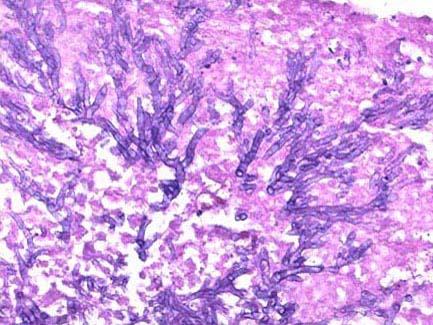

问题 糖尿病患者,男,56岁,反复刺激性咳嗽,咳棕黄色痰半年,纤支镜取活检,镜下如图所示,正确的诊断是 ( )

选项 A.肺念珠菌病 B.硅肺 C.石棉肺 D.肺放线菌病 E.肺曲菌病

答案 E